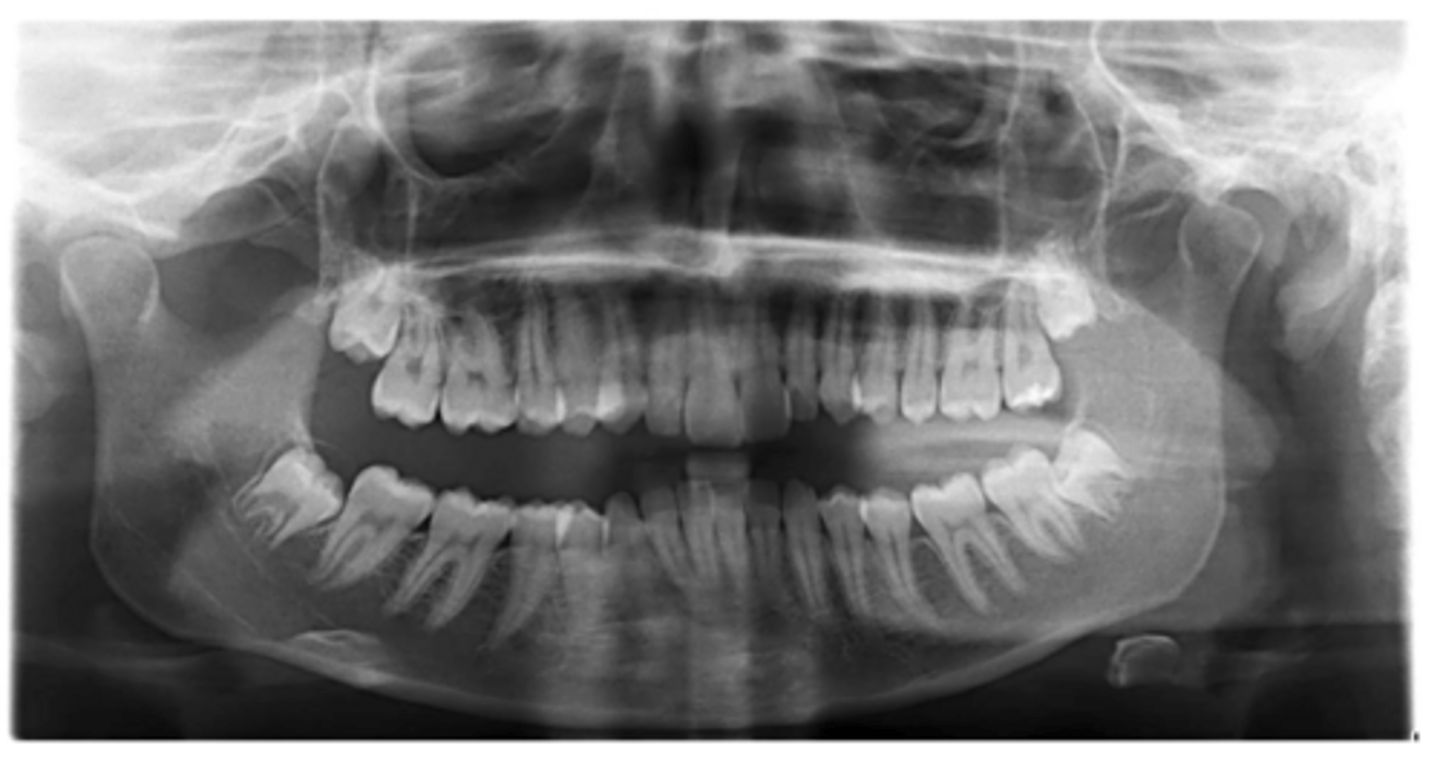

What abnormalities/concerns do you see in this pano?

Third molars and mandibular right second premolar

Are there any congenitally missing teeth in the maxillary arch?

#29 (mandibular right second premolar)

Are there any congenitally missing teeth in the mandibular arch?

mandibular right second molar

Are there any retained primary teeth?

maxillary canines

Are there any impacted teeth?

Yes

Is there crowding?

More or less

Are the condyles symmetrical?

Maybe?

Is there any pathology?

Are there any ankylosed primary teeth?

No, just one in an odd position

Is there any ectopic eruption?

No

Are there supernumerary teeth?